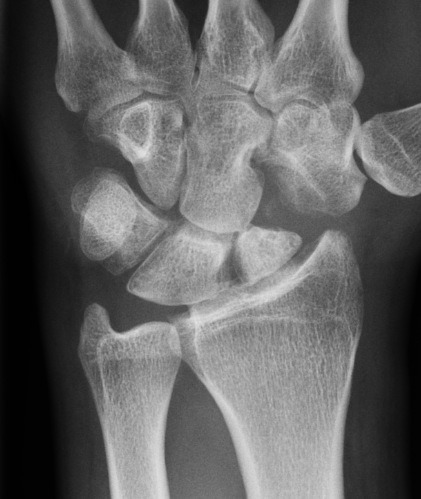

Definition

Scaphoid non union advanced collapse

Nonunion with resultant radiocarpal and midcarpal OA

Pathology

Scaphoid nonunion

- flexion deformity and abnormal joint mechanics

- radiocarpal osteoarthritis

- progresses from radial styloid / scaphoid fossa / midcarpal joint

- radiolunate joint preserved

Vender Classification

| Stage I | Stage II | Stage III |

|---|---|---|

|

Radial styloid and distal scaphoid fragment

+ Proximal scaphoid and capitate | + capitate-lunate joint |